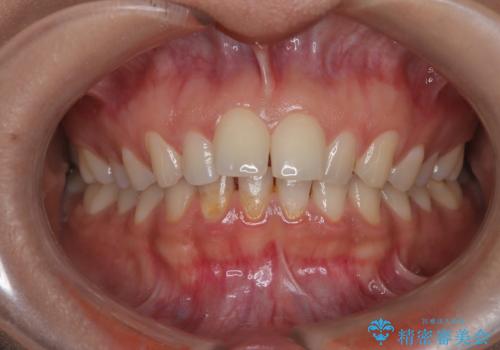

- 右上の前歯(2番)が下の歯より内側に入っている反対咬合を主訴にご来院されました。精密な検査の結果、この反対咬合を解消するためには、右上の歯列に前歯を出すためのスペースを確保する必要があると判明しました。患者様のご希望に合わせ、透明で目立たないインビザライン(マウスピース矯正)による治療計画を立案。奥歯全体を奥へ動かす遠心移動でスペースを作り、反対咬合を解消することを目指します。

今回の矯正治療では、透明なマウスピース型の装置インビザラインを使用しました。治療は、緻密なデジタル計画に基づき、奥歯から順に歯列全体を後方へ移動させる遠心移動を実施し、前歯を前に出すためのスペースを確保しました。このスペースを利用して、内側に入り込んでいた右上2番をスムーズに前方に誘導し、正常な咬み合わせへと改善。目立たないインビザラインで、機能的な咬み合わせと美しい前歯の並びを獲得していただけました。